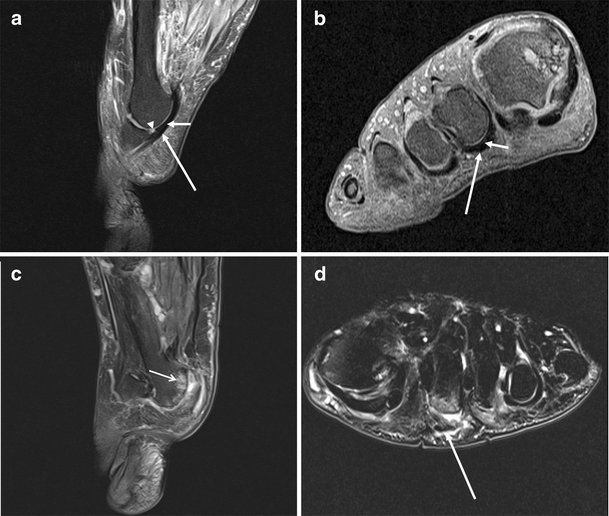

a and b (adjacent slices) Sagittal intermediate-weighted, c short axis T2-weighted fat-suppressed and d short axis T1 fat suppressed images through the second MTP joint demonstrating a tear (between arrowheads) of the plantar plate (arrow). The flexor tendon (long arrow) is adjacent to the bone distally without interposed plantar plate. There is extensive bone marrow oedema (open arrow)